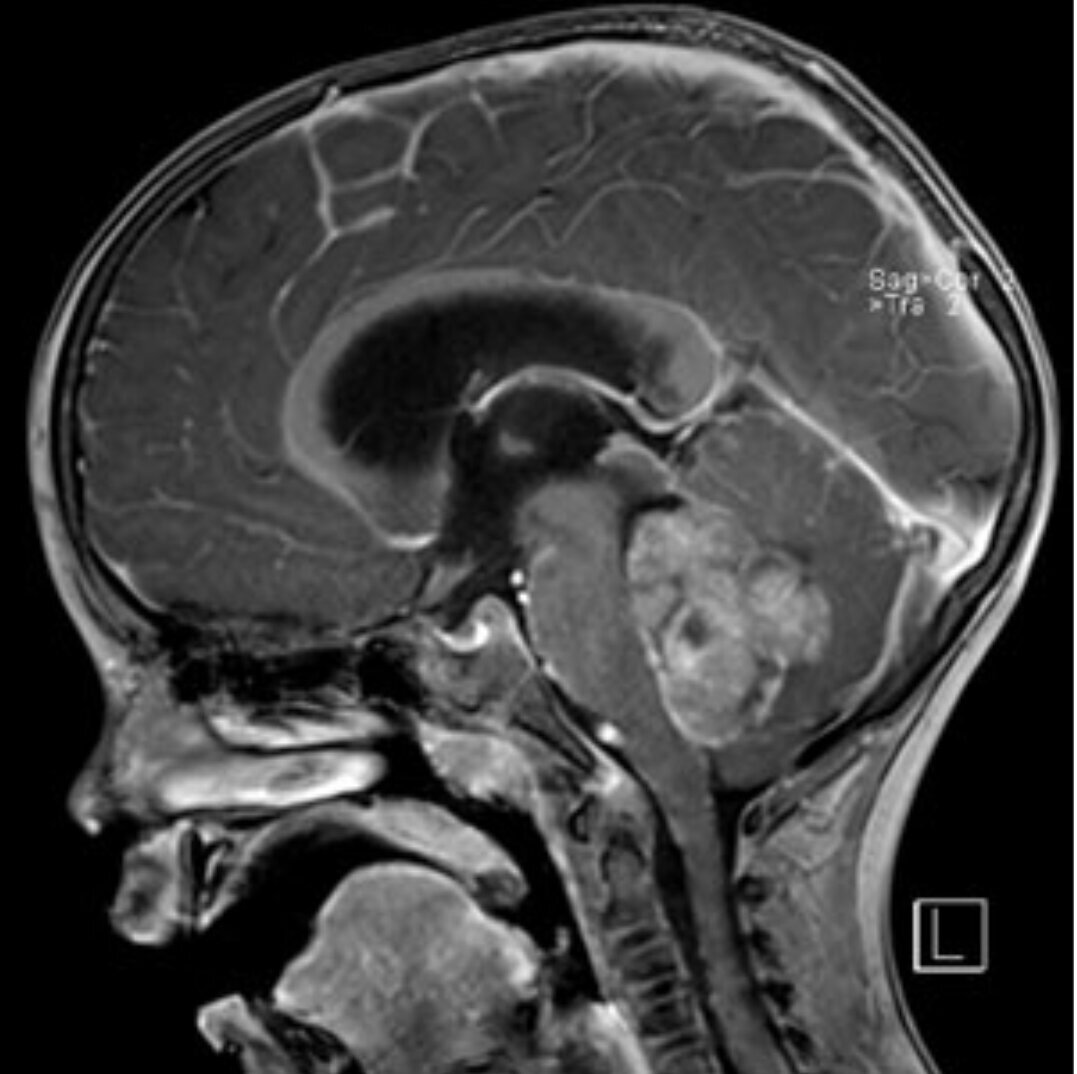

Das Medulloblastom ist der häufigste bösartige ZNS-Tumor bei Kindern. Typischerweise entwickelt er sich in der hinteren Schädelgrube – meist im IV. Ventrikel – und wächst sowohl schnell als auch infiltrierend gegen das Kleinhirngewebe. Sogenannte Abtropfmetastasen entlang der Hirnwasserwege (Liquorräume) sind möglich. Die Behandlung besteht in der möglichst kompletten chirurgischen Entfernung, gefolgt von einer adjuvanten Therapie bestehend aus Chemotherapie und bei Kindern ab ca. 4 Jahren zusätzlich Strahlentherapie. Die Behandlungsergebnisse zeigen in den letzten Jahren eine deutliche Verbesserung. Durch die beschriebene Kombinationstherapie werden heute 5-Jahresüberlebenswahrscheinlichkeiten von 70-80 % erreicht.

Diese Tumorentität ist bei Kindern vor allem im IV. Ventrikel in der hinteren Schädelgrube lokalisiert. Weitere Lokalisationen können die Seitenventrikel, der III. Ventrikel oder innerhalb des Rückenmarkskanals (intraspinal) sein. Ein zweiter Häufigkeitsgipfel ist bei Erwachsenen zwischen dem 30. und 40. Lebensjahr zu beobachten. Bei diesen Patienten findet man meist intraspinale Ependymome. Ependymome können gutartiger aber auch bösartiger Natur sein. Die Therapie richtet sich nach der Lokalisation und Dignität des Tumors. Ziel ist aber in der Regel eine komplette chirurgische Resektion. Sollte diese gelingen, ist bei den gutartigen Formen meist keine weitere Therapie nötig. Ist nur eine unvollständige Resektion möglich und/oder handelt es sich um bösartige Formen, sollte eine Nachbehandlung durch Bestrahlung und ggf. Chemotherapie erfolgen.